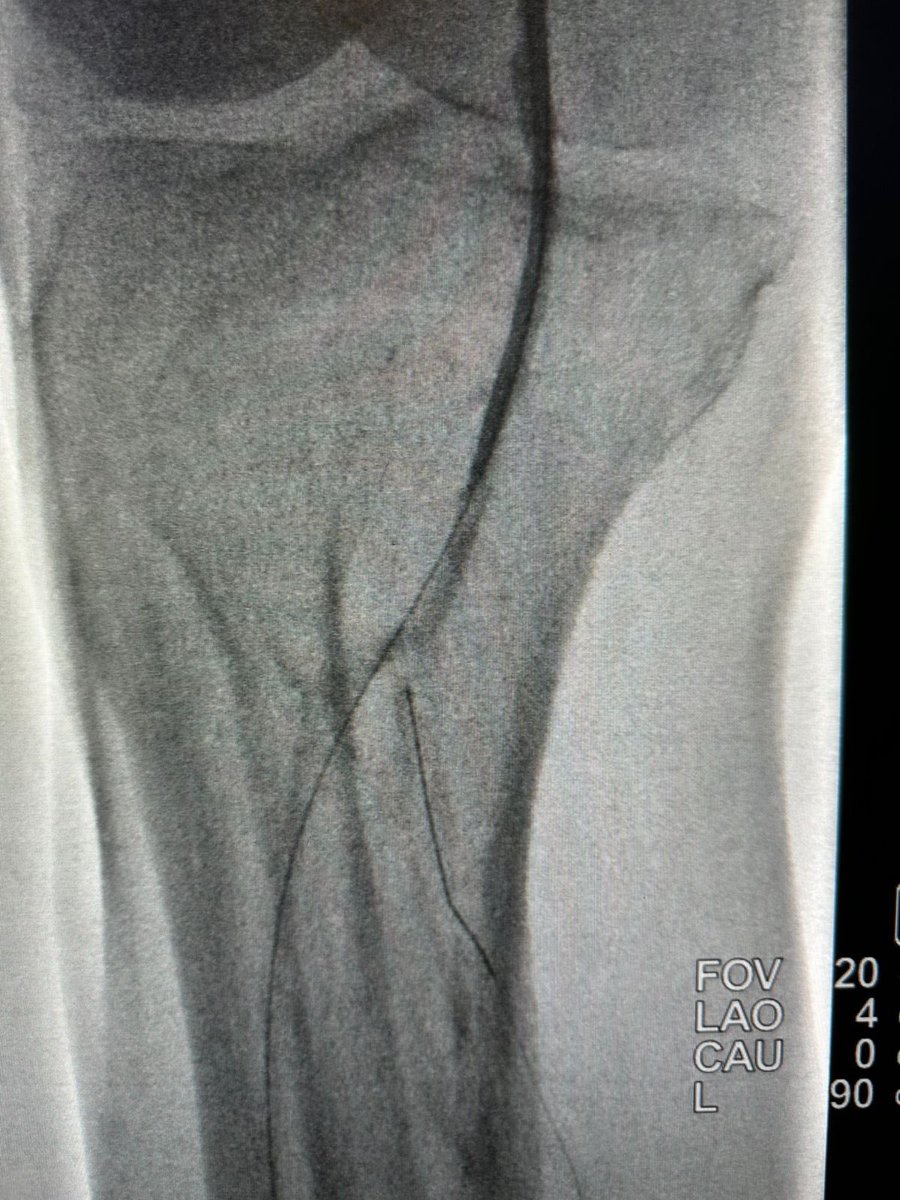

حالة من حالات نقص التروية الدموية الحاد مع وجود جرح غير ملتئم في القدم تم علاجها في وحدة #الأشعة_التداخلية بجامعة الملك سعود بالدخول من شرايين الفخذ والكاحل و إعادة فتح و توسيع الشرايين @ksumedicalcity @_KSU

د.سلطان رباح الحربي | Dr. Sultan R.Alharbi tweet mediaد.سلطان رباح الحربي | Dr. Sultan R.Alharbi tweet mediaد.سلطان رباح الحربي | Dr. Sultan R.Alharbi tweet mediaد.سلطان رباح الحربي | Dr. Sultan R.Alharbi tweet media